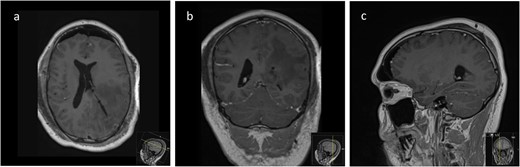

The post-operative course was uncomplicated and the patient was discharged home on post-operative day 6. Histology revealed a World Health Organization (WHO) Grade I intraventricular meningioma. Immediate post-operative MRI demonstrated complete resection of this lesion (Fig. 5), with no signs of recurrence on follow-up imaging at 8 months.

Post-operative axial (a), coronal (b), and sagittal (c) T1-weighted post-gadolinium MRI sequences of the Patient showing complete resection of the lesion with no evidence of post-operative surgical complications and complete collapse of the operative corridor pathway after removal of the tubular retractor.